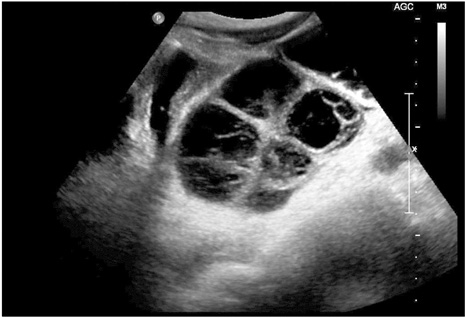

A 15-year-old boy presented at the emergency room with several episodes of nausea, vomiting, intense abdominal pain and distension. The abdominal pain was developed 7 days ago and aggravated on admission day. On initial physical examination, abdominal ileus was suspected. He did not complain of any signs of gastrointestinal bleeding, such as melena or hematochezia. His body temperature was 37.1℃ and laboratory tests including complete blood counts, liver and renal function were within normal range. Ultrasonography and contrast-enhanced CT revealed an about 13 cm sized multiseptated cystic mass in pelvic cavity (

Fig. 1). The mass was entirely cystic appearance without any enhancing solid portion. The cystic lumen showed echogenic internal hemorrhage on ultrasonography. The overlying small intestine was diffusely dilated. On operation, a huge cystic mass was palpated in the jejunum about 15 cm below from the ligament of Treiz. He underwent segmental resection and primary anastomosis, under the diagnosis of intestinal obstruction by small bowel tumor. On gross examination of the specimen, the mucosa was intact but slightly hyperemic and a well demarcated submucosal outbulging mass measuring 13.5×7.0×5.5 cm was noted. The external surface of mass was multilobulated and congested. On section, the mass was multilocular cystic appearance separated by fibrous septa and contained bloody materials (

Fig. 1Ultrasonographic finding. Ultrasonography revealed a multiseptated cystic mass with internal hemorrhage in pelvic cavity.